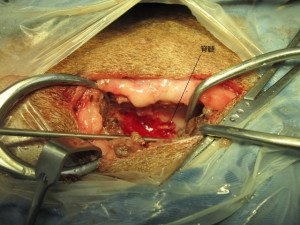

椎間板物質除去後です。

脊髄が見えるようになりました。